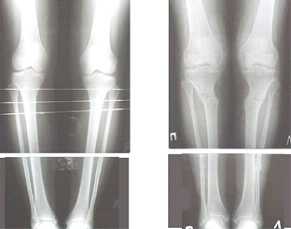

Судя по снимку у девушки имеется внутренняя установка надколенников...

Как у нее с торсионным статусом? Бедро? Голень? КТ? Торсиометры? А то, куда будут

смотреть надколенники после вашей коррекции - тоже существенный

косметический момент. Или не так?

Клинически глядел - вроде нету большой торсии.

AVM> Судя по снимку у девушки имеется внутренняя установка надколенников...

AVM> Как у нее с торсионным статусом? Бедро? Голень? КТ? Торсиометры?

Похоже, немного есть. Думаю пренебречь.